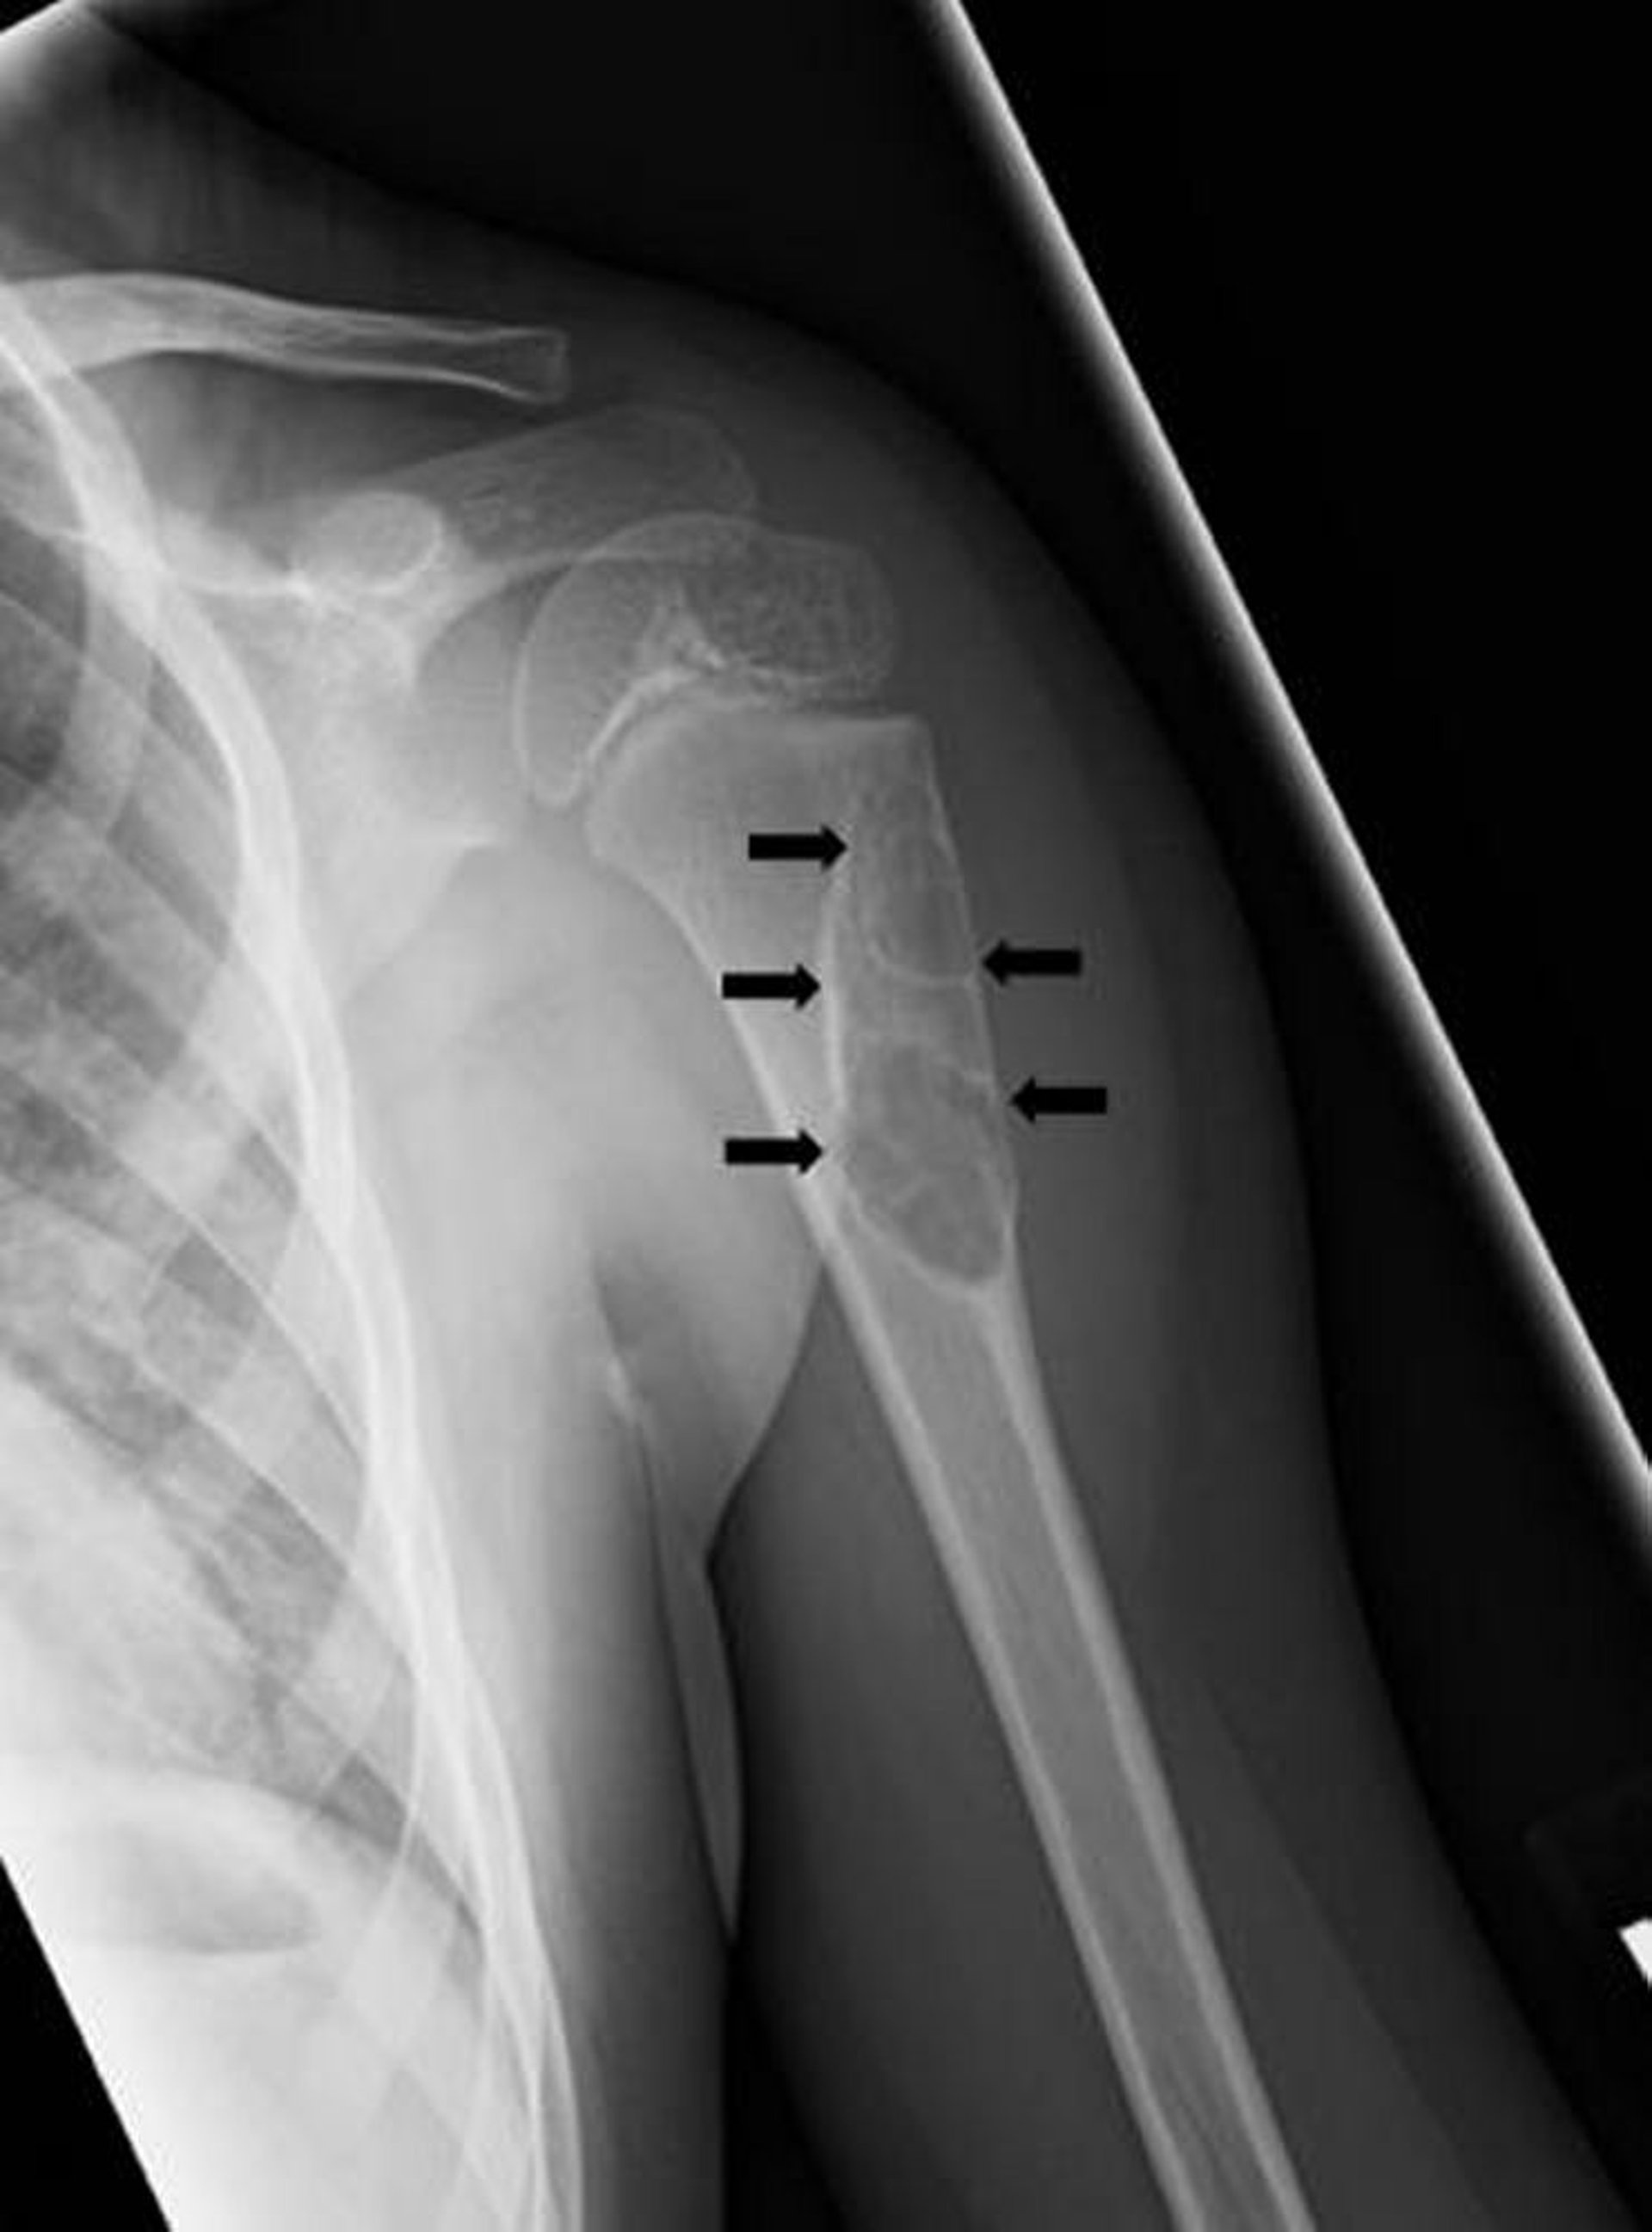

Nang xương đơn độc

Phim chụp X-quang này cho thấy tổn thương dạng nang (mũi tên) ở xương cánh tay ở trẻ em phù hợp với nang xương một ngăn.

Hình ảnh do bác sĩ Michael J. Joyce, và bác sĩ Hakan Ilaslan cung cấp.